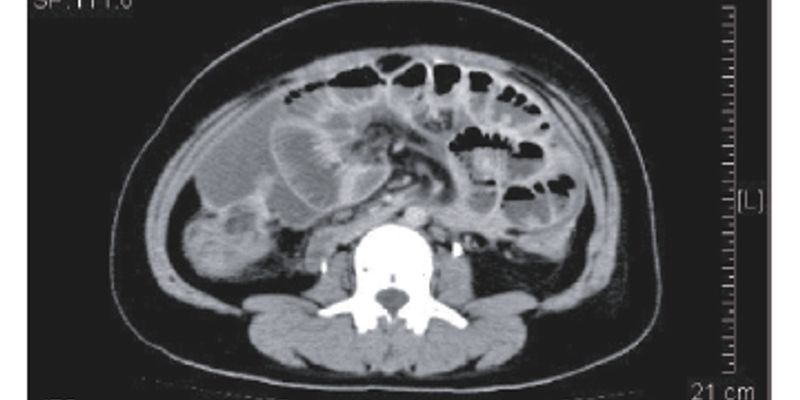

结直肠癌(CRC)远处转移是患者的主要死因。本文深度解读CRC基因组进化模式,揭示了转移灶的三种规律:分支、有序和播散转移。了解为何必须进行动态基因检测,R0切除手术时机的重要性,以及多学科协作(MDT)如何优化转移性CRC的治疗方案。同时探讨了晚期治疗的困境与未来新靶点探索,并强调了生活方式在CRC预防中的关键作用。 Read More... "结直肠癌转移新指南:基因组进化模式如何重塑肝转移治疗决策与R0切除时机"